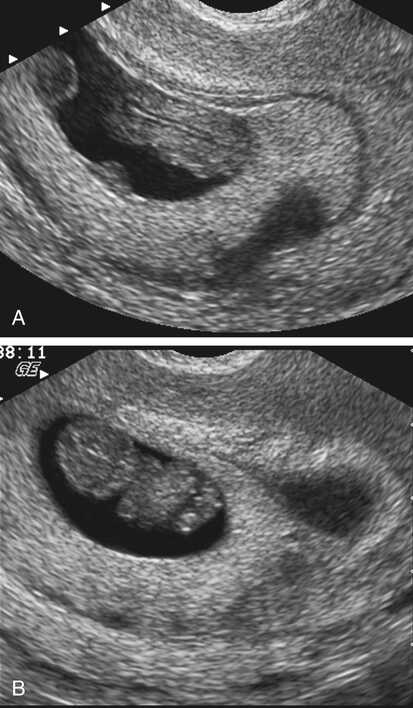

USG dengan gambaran perdarahan atau kantung haid abnormal | Sumber: Radiology Key

Meski Anda mungkin merasakan banyak ciri positif di atas, penting untuk selalu waspada terhadap beberapa kondisi darurat.

Tanda-tanda ini membutuhkan penanganan medis segera karena dapat mengindikasikan risiko serius, termasuk ciri-ciri janin tidak berkembang.

Berikut adalah tanda bahaya kehamilan trimester 1 yang wajib Anda perhatikan:

- Pendarahan Vagina Hebat: Pendarahan yang banyak, berwarna merah terang, dan disertai gumpalan dapat menjadi tanda awal keguguran.

- Nyeri Perut Bagian Bawah yang Parah: Nyeri perut yang hebat, terutama jika hanya terasa di satu sisi, bisa menjadi indikasi kehamilan ektopik (janin tumbuh di luar rahim) atau keguguran.

Jika Anda mengalami kondisi-kondisi di atas, apalagi jika disertai dengan detak jantung janin yang tidak terdengar—yang menjadi ciri-ciri janin tidak berkembang—segera konsultasikan ke dokter kandungan.